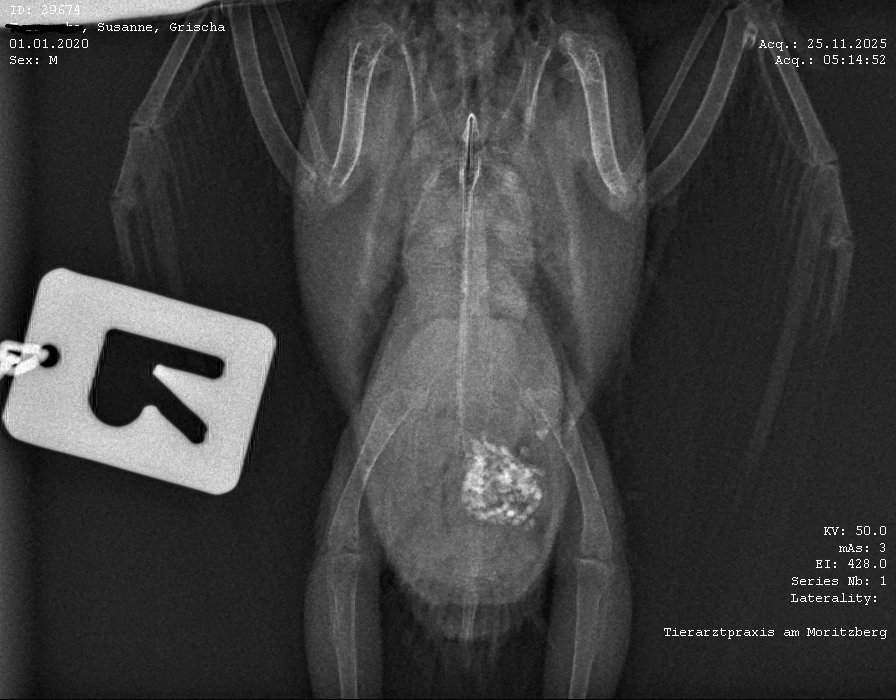

Grische4ka Опубликовано 27 ноября, 2025 #1 Опубликовано 27 ноября, 2025 Здравствуйте, помогите пожалуйста разобрать рентген. Заметны ли какие то изменения? Волнистик быстро и тяжело лишит. Паразитов и бактерий в помете нету. Но очень важно понять есть ли проблемы с внутренними органами. Заранее спасибо!